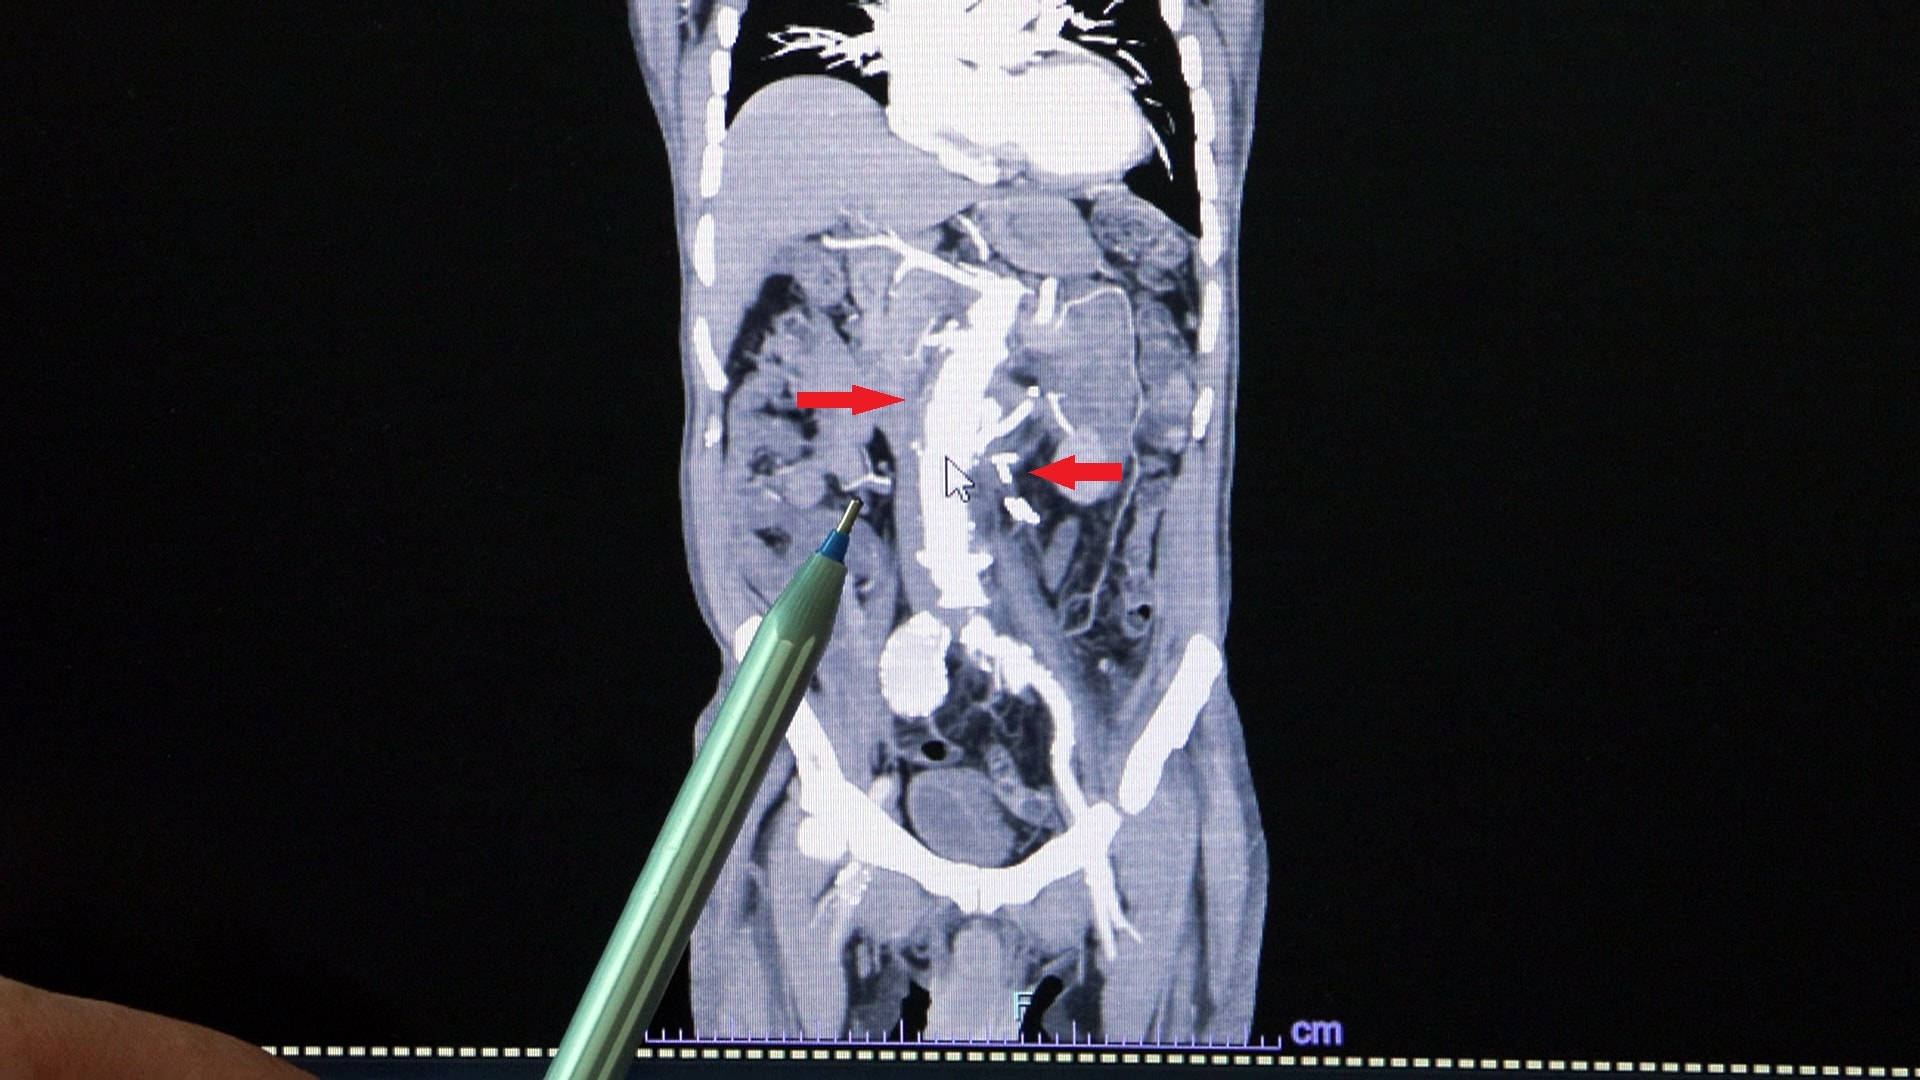

– Sıtkı Bey bize 5 yıl önce geldi, 3 ay önce bypass olmuştu. Karnında bir baloncuk şüphesi vardı. 3 santim olması gereken ana damar çapının yaklaşık 10 santime ulaştığını gördük. Anevrizma dediğimiz bu durum, aort damarının ya göğüs bölgesinde ya da karında olur. Ama Sıtkı Bey’de 60 santimlik aort damarının hepsinde genişleme vardı. Bütün iç organları ve bacakları besleyen hayati organ damarları da o baloncuğun içinden çıkıyordu. Patladı patlayacak durumdaydı.

– Biz o endişeyle ameliyat planlamasını yaptık. Genel cerrah, ürolog ve 3 kalp damar cerrahı girdik ameliyata. Yaklaşık 8-9 saat sürdü. İç organların hepsini ayrı ayrı sanki kan alıyorlarmış gibi, yapay beslenme ünitelerine bağladık. Sonra ana damarla iç organlara giden damarları tek tek birleştirdik. En sıkıntılı aşama buydu çünkü böbrek yetmezliği, karaciğer yetmezliği, bacaklarda felç, bacakların kesilmesi risklerinin hepsi vardı. Ameliyattan sonra en güzel an, ayaklarını oynatabiliyor olmasıydı. Bundan 2 yıl sonra sağ kasığı, ondan 6 ay sonra sol kasığı, ondan da 2 yıl sonra da göğüs duvarında ve çapın 7,5 santime ulaşan aort damarını kapalı ameliyatla tedavi ettik.

Korktuk acaba bütün o bölgeyi endovasküler stent dediğimiz yapay damarla kapatırsak felç olabilir mi diye. En son, 17-18 santimlik düz bir stent koyarak bütün göğüs duvarındaki anevrizmayı kapattık. Son ameliyatı da sol kasıkta olan baloncuğu için yine yine kapalı yöntemle yaptık. Sıtkı Bey’in kalpten çıkan ve kasıklara kadar giden 60 santimlik ana damarının yüzde 96’sına müdahale edildi. Bunun 90’ı yani yaklaşık 50-52 santimlik kısmı da yapay damarla değiştirilmiş oldu.